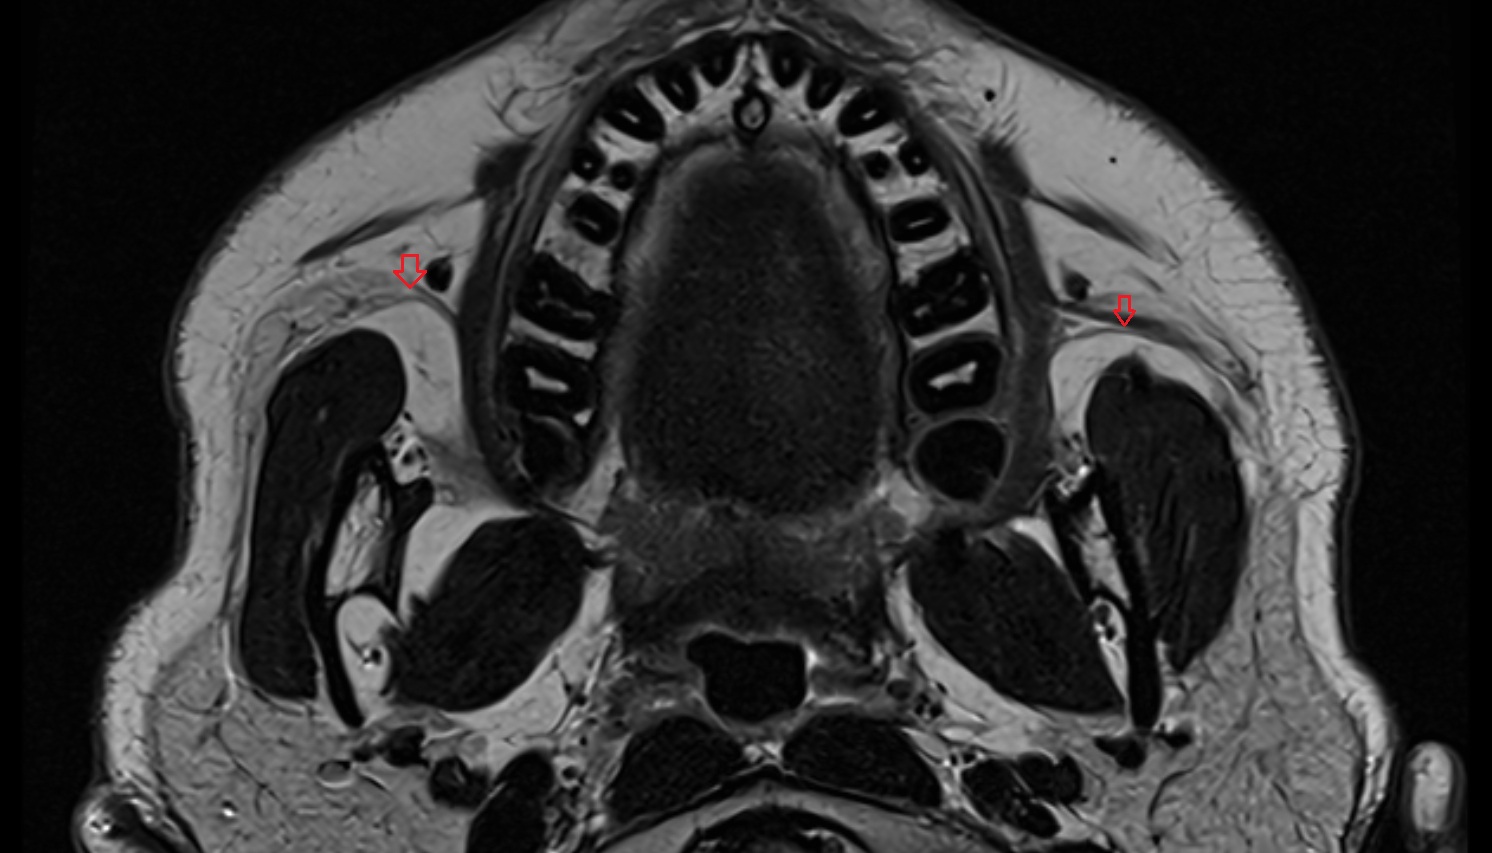

- Temporomandibular joint

- Mandibular condyle

- Mandibular fossa

- Lateral pterygoid muscle

- Masseter muscle

- Medial pterygoid muscle

- Temporalis muscle